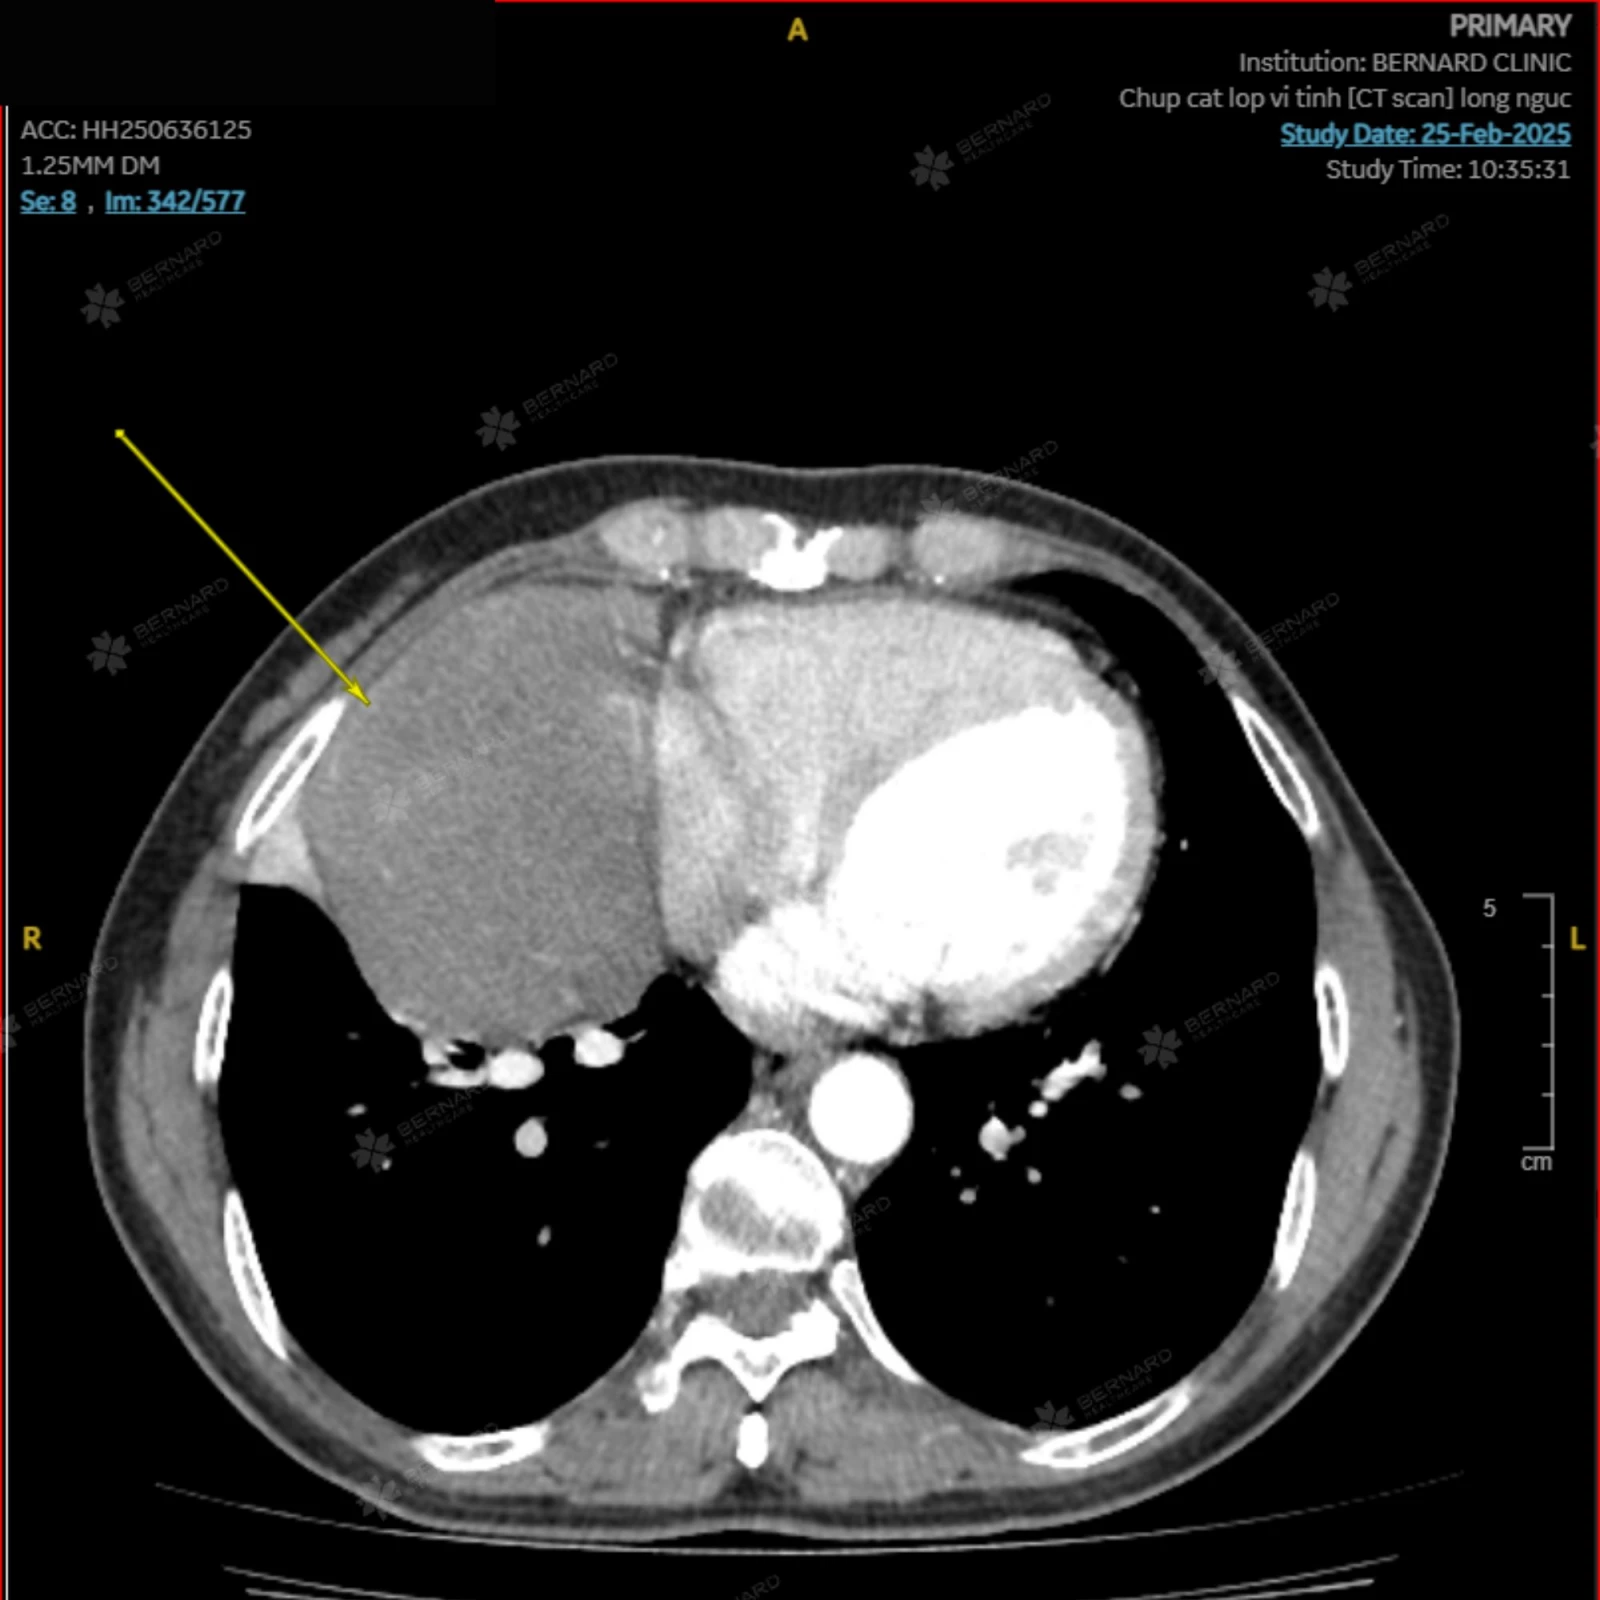

Nhận thấy bất thường, ngay sau đó, bác sĩ Bernard đã nhanh chóng chỉ định bệnh nhân thực hiện chụp cắt lớp vi tính (CT scan) lồng ngực có tiêm thuốc cản quang để đánh giá chi tiết hơn. Đây là bước quan trọng nhằm phát hiện và đánh giá tổn thương rõ hơn mà X-quang có thể bỏ sót.

Kết quả CT Scan khi quét qua trung thất vị trí trung tâm cho thấy: Có khối tổn thương choán chỗ lớn trung thất giữa (P), sát màng ngoài tim (P), bờ giới hạn khá rõ, trơn đều, có kích thước khoảng 65 x 87 x 110mm (ngang x trước sau x cao), đậm độ trung bình không đồng nhất, bắt thuốc tương phản không đồng nhất. Hình ảnh này gợi ý một số chẩn đoán phân biệt: U trung thất (Fibroma, Mesothelioma hoặc di căn). Đáng lo ngại hơn, khối tổn thương đã gây đè ép dẫn đến xẹp phổi thụ động, một dấu hiệu cần được can thiệp kịp thời và theo dõi chặt chẽ.